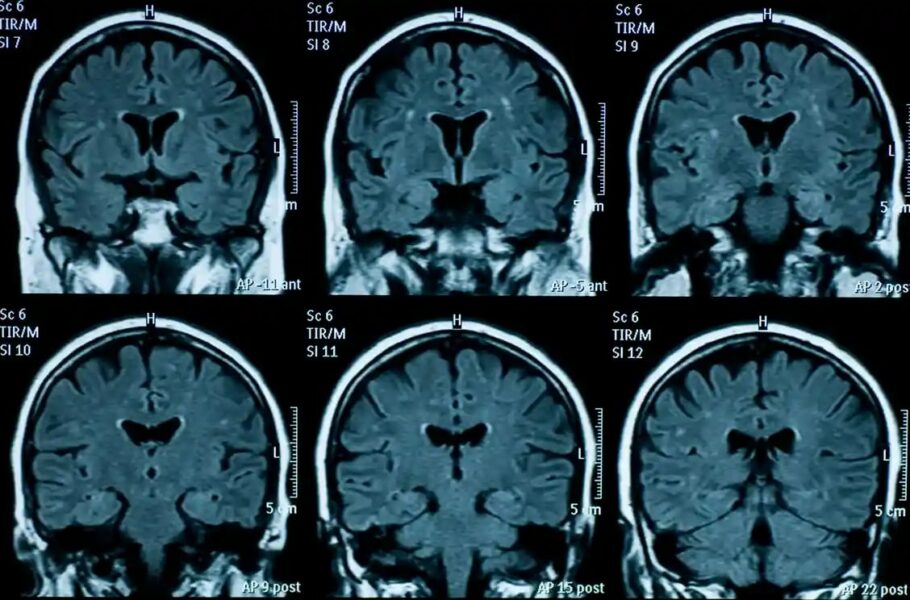

پژوهشی جدید: مغز نوجوانانی که در دوران قرنطینه کرونا زندگی کردهاند، سریعتر پیر میشود زمان انتشار: 4 دسامبر 2022 ساعت 7:04 دسته بندی: فناوری شناسه خبر: 80731 زمان مطالعه: 1 دقیقه پژوهشی جدید: مغز نوجوانانی که در دوران قرنطینه کرونا زندگی کردهاند، سریعتر پیر میشود حتما بخوانید : سامسونگ تا 2025 احراز هویت با اثر انگشت را 2.5 میلیارد برابر ایمنتر میکند مجله خبری gsxr